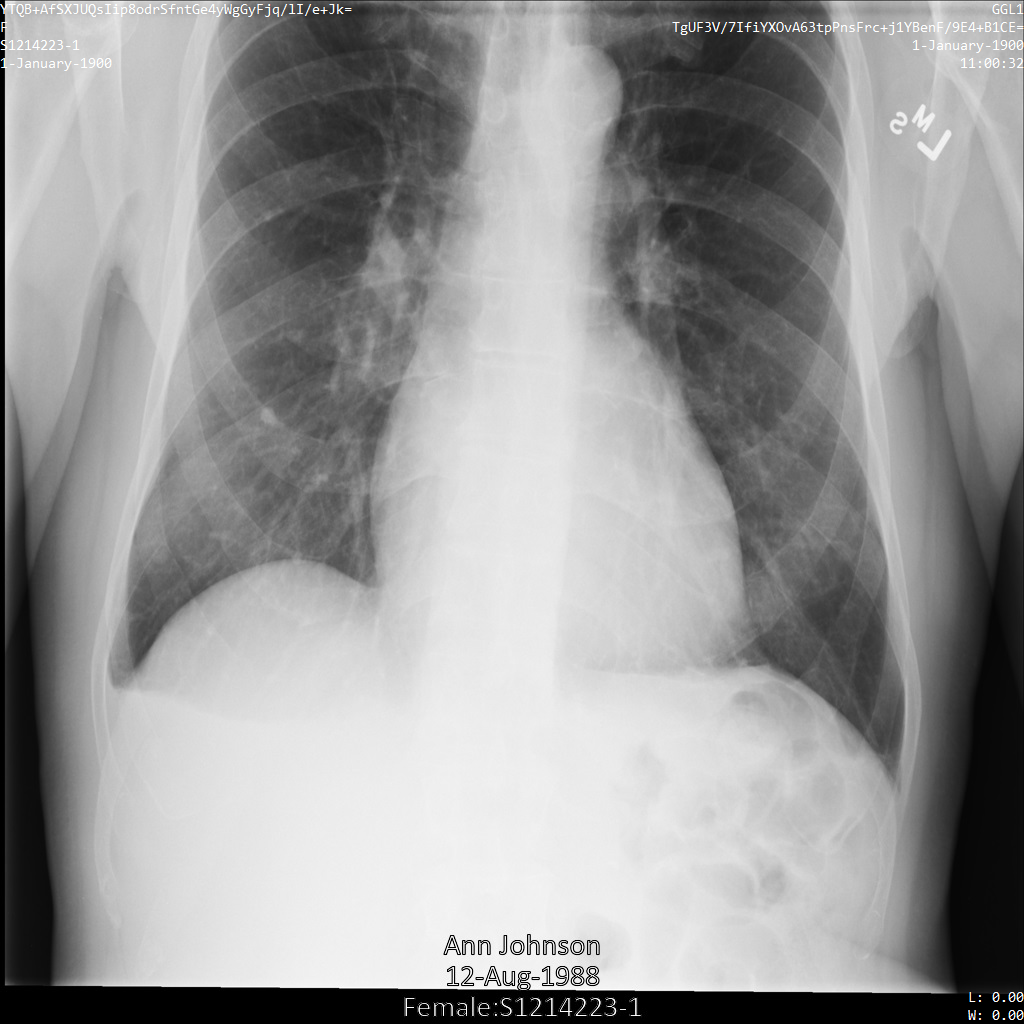

L'immagine seguente mostra una radiografia non oscurata di un paziente:

Dopo aver inviato l'immagine all'API Cloud Healthcare utilizzando

l'opzione REDACT_SENSITIVE_TEXT, l'immagine

viene visualizzata nel seguente modo:

Puoi notare che si è verificato quanto segue:

- Il

PERSON_NAMEin basso a sinistra dell'immagine è stato oscurato - Il

DATEin basso a sinistra dell'immagine è stato oscurato

Il sesso del paziente non è stato oscurato perché non è considerato testo sensibile secondo i tipi di informazioni DICOM predefiniti.